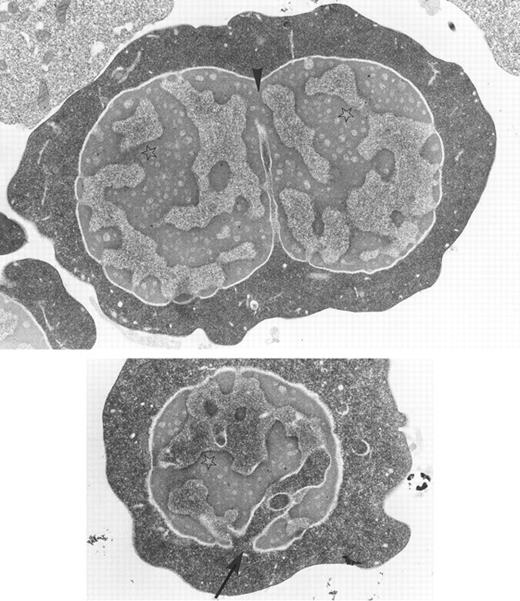

Bone marrow erythroblasts from a patient with congenital dyserythropoietic anemia type I: chromatin bridges between two adjacent nuclear lobes (arrow-head), spongy appearance of the chromatin (stars), and widening of nuclear pores with nucleus invasion by the cytoplasm (arrow) are characteristic ultrastructural features of the disease. Original magnification × 10,400. (Courtesy of Elisabeth M. Cramer and Josette Guichard, INSERM U.91, Hopital Henri Mondor, 94010 Creteil, France.)